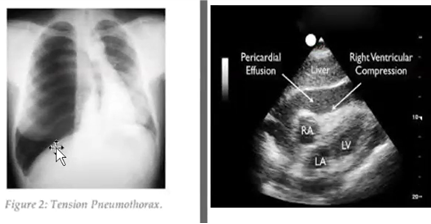

Vilka är de två vanligaste övergripande orsakerna till B-problem?

B-problem

När kan detta bli aktuellt och hur fungerar det?

Obehandlad pneumothorax, subcutana emfysem, aspirationsrisk, medvetandesänkning

Vad ska undvikas vid ovan?

CPAP och bilevel behandling